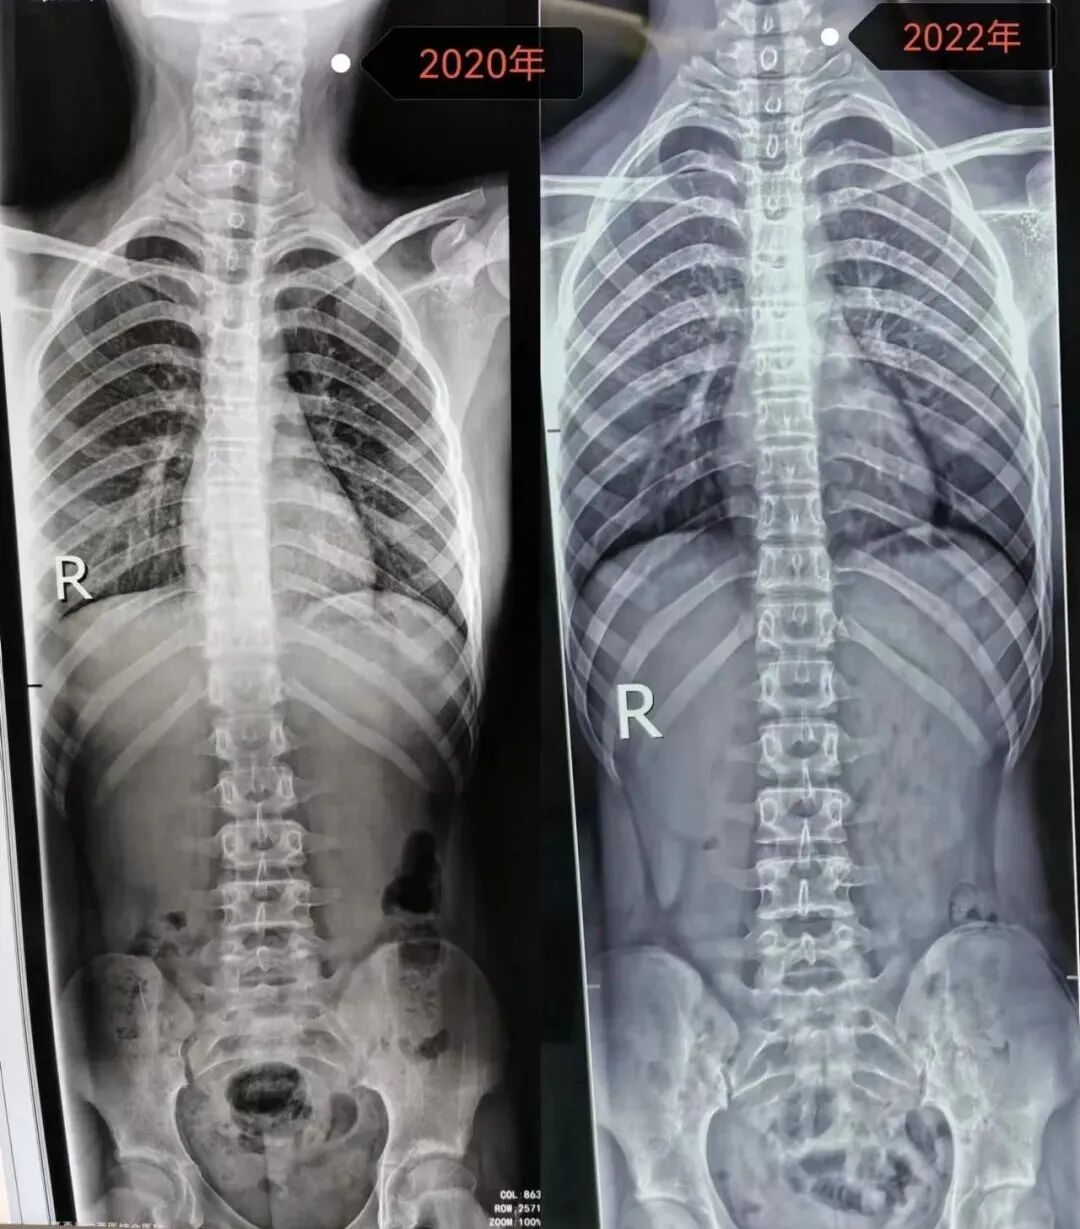

万一怀疑孩子有问题,一定要到医院进行专业的脊柱侧弯筛查,目前诊断脊柱侧弯的金标准是站立位拍脊柱全长X线片正侧位。

我们要做的,就是在明白疾病自然进程的前提下积极对症干预,生长发育只有一次,抓住黄金矫正期。

矫正前 Vs. 矫正后

前后对比